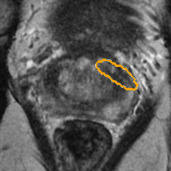

Radiomics uses quantitative medical imaging features to predict clinical outcomes. Currently, in a new clinical application, finding the optimal radiomics method out of the wide range of available options has to be done manually through a heuristic trial-and-error process. In this study we propose a framework for automatically optimizing the construction of radiomics workflows per application. To this end, we formulate radiomics as a modular workflow and include a large collection of common algorithms for each component. To optimize the workflow per application, we employ automated machine learning using a random search and ensembling. We evaluate our method in twelve different clinical applications, resulting in the following area under the curves: 1) liposarcoma (0.83); 2) desmoid-type fibromatosis (0.82); 3) primary liver tumors (0.80); 4) gastrointestinal stromal tumors (0.77); 5) colorectal liver metastases (0.61); 6) melanoma metastases (0.45); 7) hepatocellular carcinoma (0.75); 8) mesenteric fibrosis (0.80); 9) prostate cancer (0.72); 10) glioma (0.71); 11) Alzheimer's disease (0.87); and 12) head and neck cancer (0.84). We show that our framework has a competitive performance compared human experts, outperforms a radiomics baseline, and performs similar or superior to Bayesian optimization and more advanced ensemble approaches. Concluding, our method fully automatically optimizes the construction of radiomics workflows, thereby streamlining the search for radiomics biomarkers in new applications. To facilitate reproducibility and future research, we publicly release six datasets, the software implementation of our framework, and the code to reproduce this study.

翻译:放射科使用定量医学成像特征来预测临床结果。目前,在一个新的临床应用中,通过一个超常试验和高压过程,通过人工操作,从广泛的现有选项中找到最佳放射法。在本研究中,我们提议了一个框架,自动优化每个应用程序的放射工作流程的建设。为此,我们将放射作为模块工作流程,并包括每个部件的大量通用算法。为了优化每个应用程序的工作流程,我们使用随机搜索和聚合的自动机学习方法。我们用12种不同的临床应用来评估我们的方法,结果在曲线下应用的以下领域:1) 脂色瘤(0.83);2) 脱氧型纤维瘤(0.82);3 初级肝脏肿瘤(0.80);4 气肠肿瘤(0.77)、5 彩虹肝脏移植(0.61); 6 脑膜细胞变异常(0.45); 7) 肝细胞变异常(0.8) 脑纤维变异位(0.80); 9) 直径直线型癌症(0.74) 和头型癌症(0.77) 直径研究(10) 。